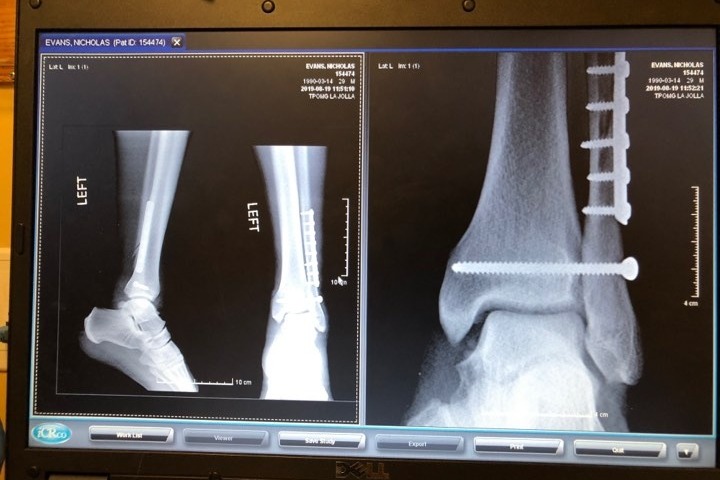

Just over two hours later, Dr. Thunder walked out and let me know he put a steel plate and 8 pins in Nicks fibula, the ligament that keeps his bones together was shredded so he laid it over, and a pin to hold the bones together that will get taken out in 6-8 weeks.